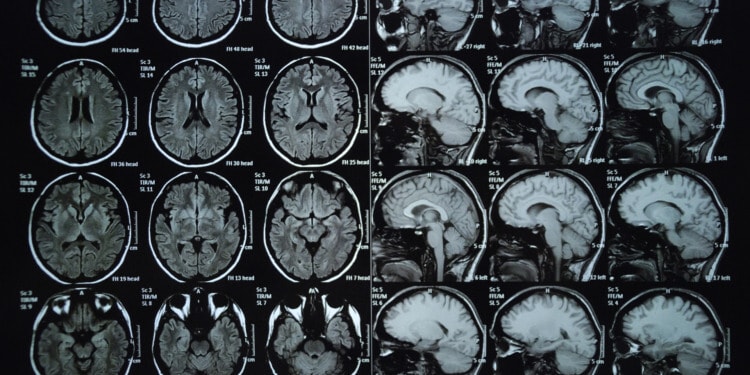

For those who were pregnant at the time, enduring these extreme conditions wasn’t just uncomfortable — it may have left a lasting imprint on their children’s brains. That’s according to a new study published on Wednesday in the peer-reviewed journal PLOS One. Using MRI scans, researchers at Queens College, City University of New York, found that children whose mothers lived through Superstorm Sandy had distinct brain differences that could hinder their emotional development. The effects were even more dramatic when people were exposed to extreme heat during their pregnancy, in addition to the tropical storm, the researchers found.

The study analyzed brain imaging data from a group of 34 children, approximately 8 years old, whose mothers were pregnant during Superstorm Sandy — some of whom were pregnant at the time that Sandy made landfall, and some of whom were exposed to heat 95 degrees F or higher during their pregnancy. While the researchers didn’t find that heat alone had much of an impact, living through Superstorm Sandy led to an increase in the basal ganglia’s volume, a part of the brain that deals with regulating emotions.

While that larger size could be a compensation in response to stress, changes in the basal ganglia have been linked to behavioral challenges for children, such as depression and autism, DeIngeniis said.

DeIngeniis’ study offers concrete evidence of how climate-charged events can affect the brain, Barkin said. “People have a hard time sometimes with mental health, because it’s not like you can take an X-ray and see a broken bone.” But it’s easier to understand imaging showing a difference in brain volume based on exposure to environmental stress, she said.